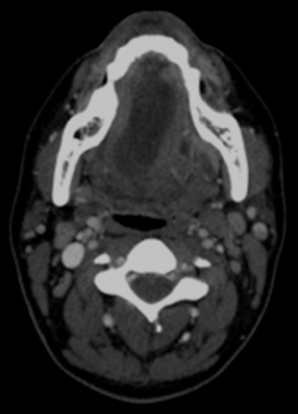

En el examen extraoral presentaba simetría facial, sin adenopatías palpables ni masa cervical evidente. Al realizar el examen intraoral se manifiesta una lesión ovoide de 7 × 4 cm en la región sublingual derecha, unilateral, que no cruza la línea media; fluctuante, de color translúcido edematoso e indoloro, que eleva y desvía la lengua al lado contralateral (fig. 1). Se realizó una hipótesis diagnóstica de ránula intraoral, la cual se complementó mediante examen imagenológico tomográfico (TC) con medio de contraste para confirmar la presencia de una lesión quística unilocular, ovalada, de baja densidad, confinada al espacio sublingual, además de evaluar su extensión anatómica confirmando su ubicación intraoral/superficial (fig. 2).